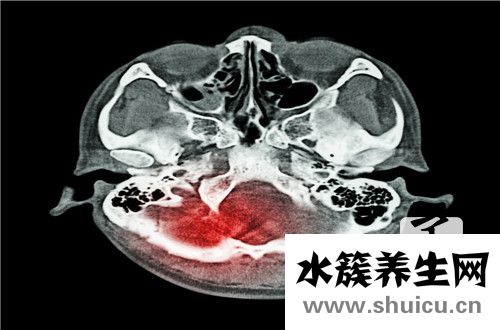

許多細菌很容易感染人的傷口,如果被感染,對人的身體有很大的影響。作為人體最重要的部分,如果感染發生在頭部,頭部將會產生難以想象的后果。然而,顱內感染可以由許多情況引起,所以如果你在日常生活中不...